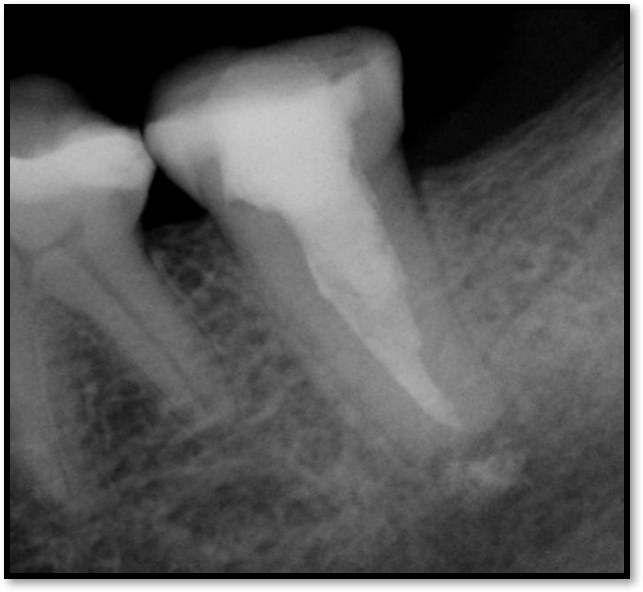

Adjacent Structures

If a tooth stands alone, greater forces will be placed on it because it has no adjacent teeth to provide support. This situation will affect the decision-making process for placing a post. Figure 3 shows a tooth that was on an island and would be having three implants placed in front of it. The tooth would take a much greater beating than another tooth that had support proximally. Even though it had a good root canal, the clinician would need to account for whether the tooth would last until the implants integrated. Figure 4 shows a case that would quickly proceed to implants. The patient had a less-than-ideal bridge for over a decade, with decent endodontics and functionality. There was also an overhang on the premolar. The post was not ideal in this case because there was one distal canal and not all the gutta-percha was removed from it. An intimate fit should be the goal with the post and the walls. Whether using a threaded or non-threaded post, there should not be excess gutta-percha because it is not as solid as the tooth and will lead to greater movement. That movement on the tooth and bridge will create too much force and result in demise.

Fig 3. Tooth on an island.

Figure 3